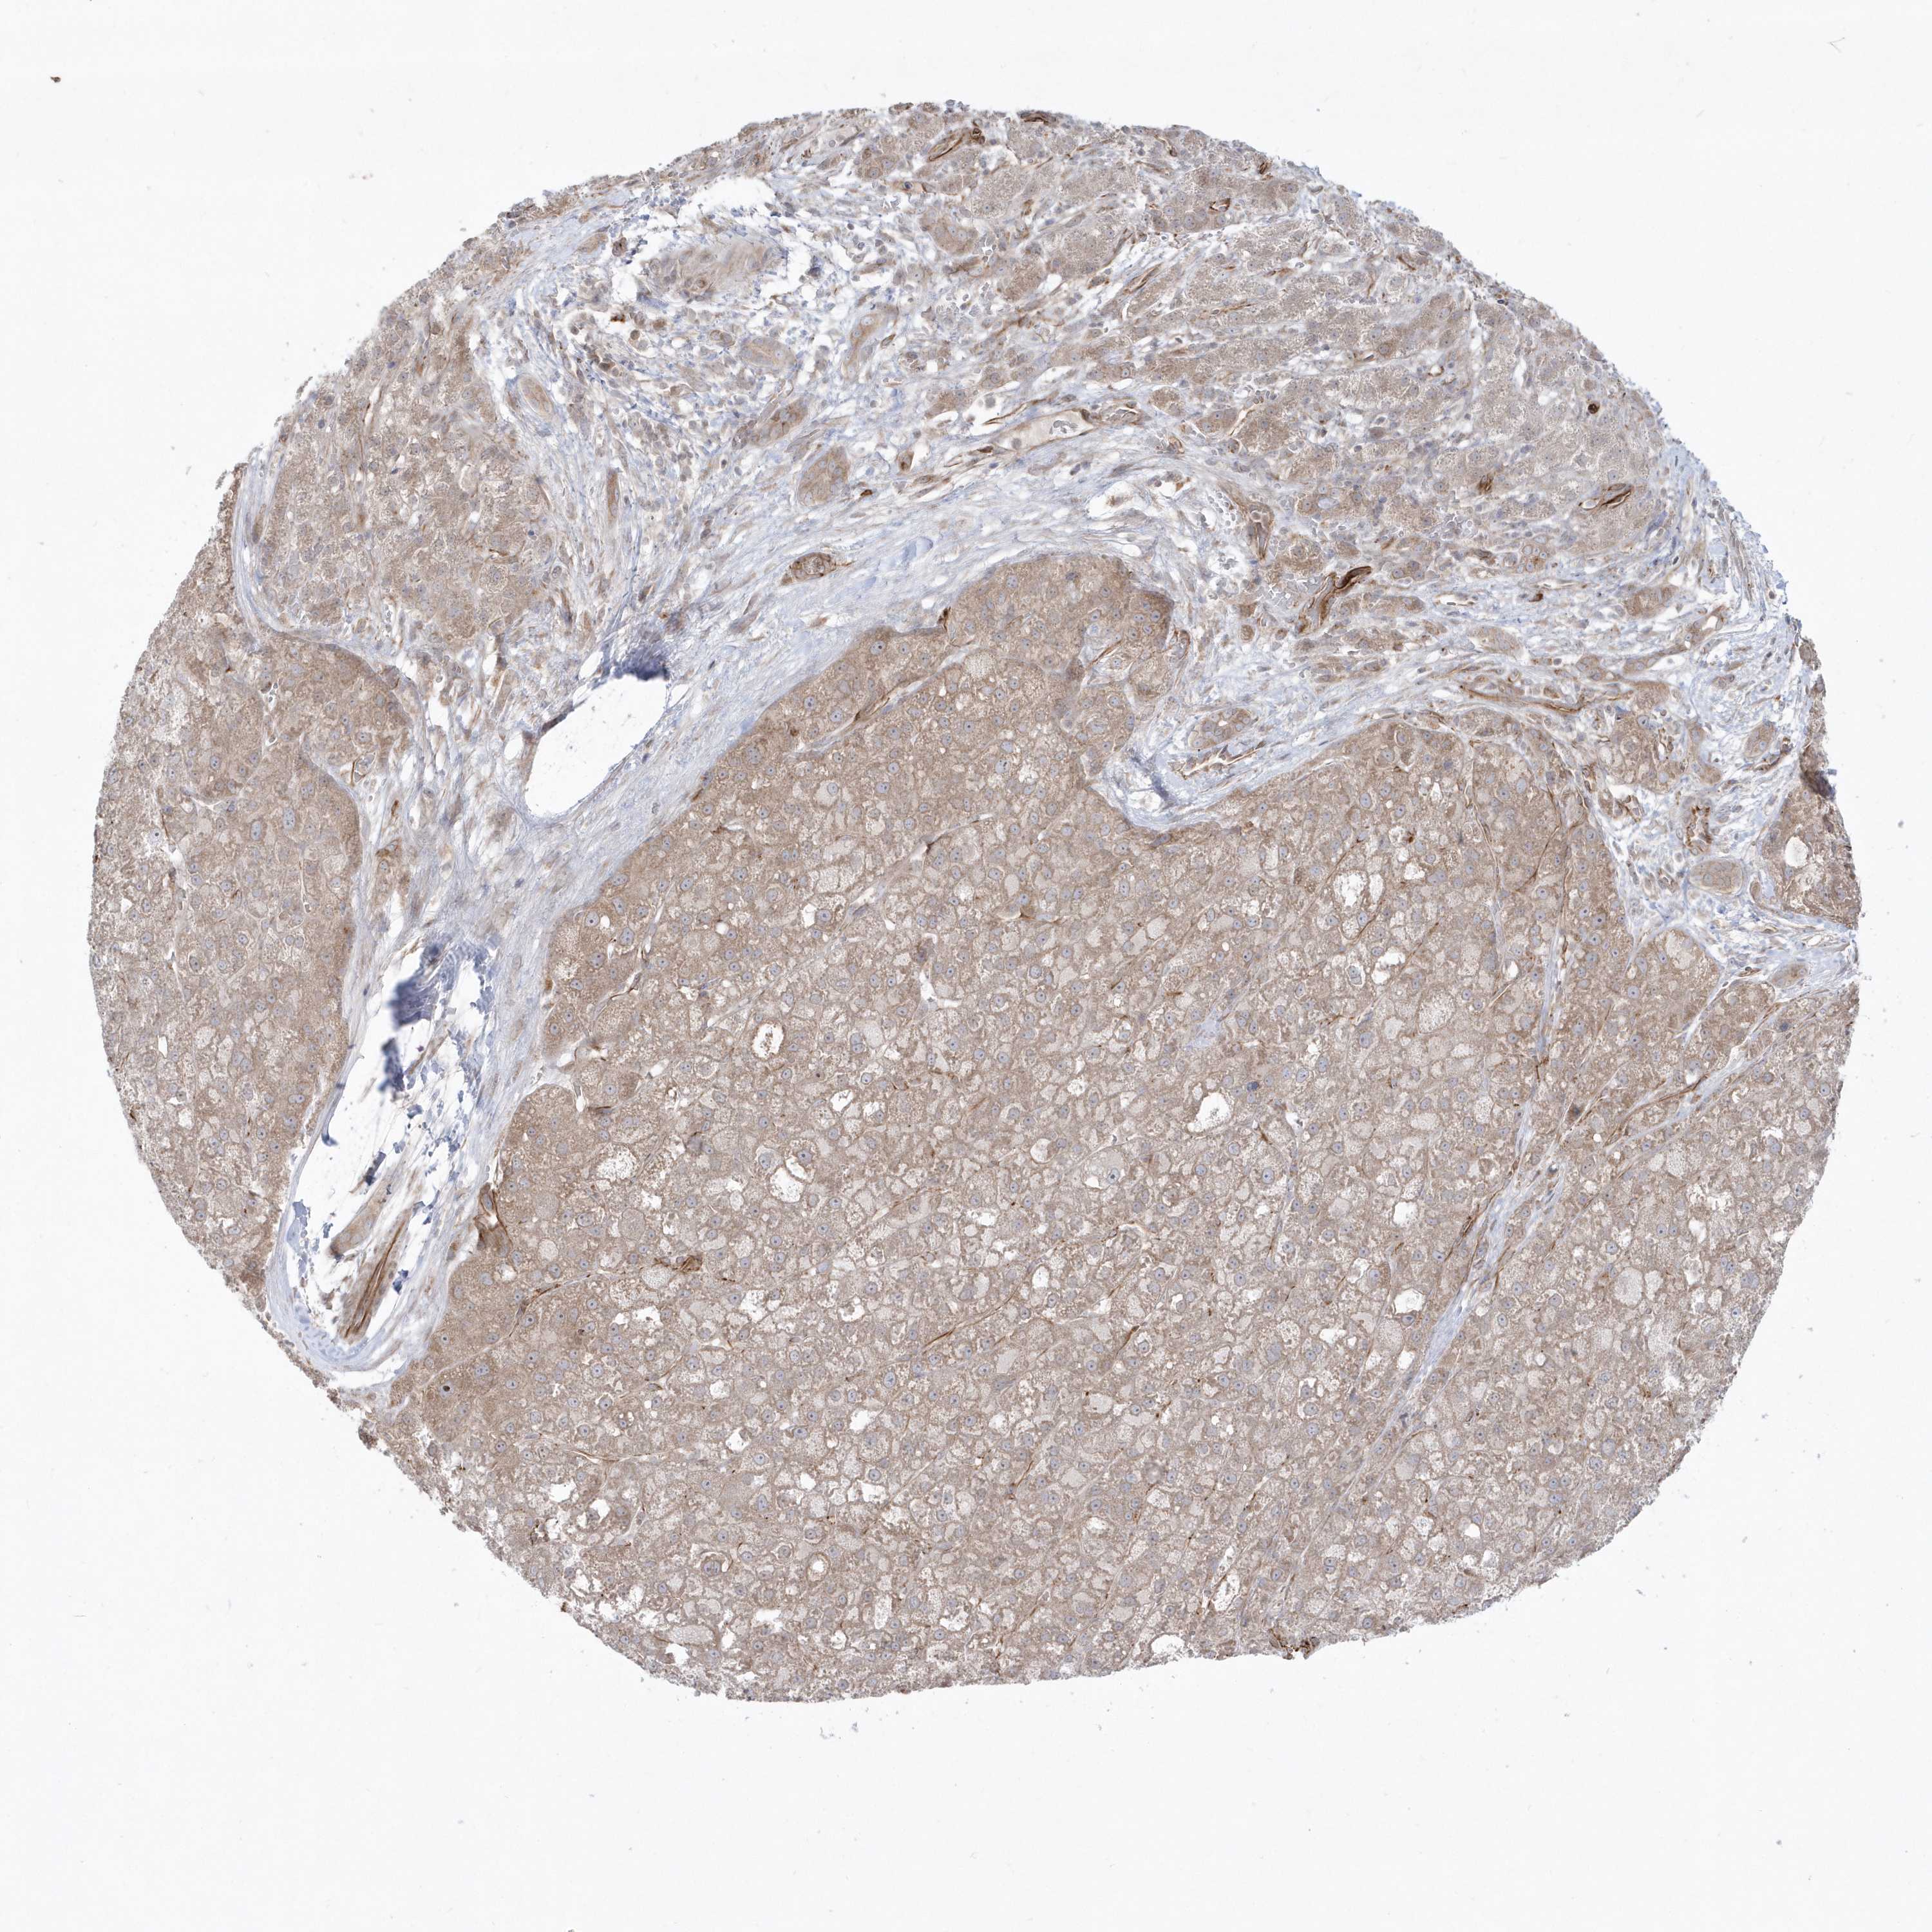

LIVER CANCER - Protein expressioni

A mouse-over function shows sample information and annotation data. Click on an image to view it in a full screen mode. Samples can be filtered based on level of antibody staining by selecting one or several of the following categories: high, medium, low and not detected. The assay and annotation is described here.

Note that samples used for immunohistochemistry by the Human Protein Atlas do not correspond to samples in the TCGA dataset.

Antibody stainingi

Antibody staining in the annotated cell types in the current human tissue is reported as not detected, low, medium, or high, based on conventional immunohistochemistry profiling in selected tissues. This score is based on the combination of the staining intensity and fraction of stained cells.

Each image is clickable and will lead to virtual microscopy that enables deeper exploration of all samples and also displays staining intensity scores, fraction scores and subcellular localization as well as patient and tissue information for each sample.

Antibody HPA036160

Staining

High

Medium

Low

Not detected

Intensity

Strong

Moderate

Weak

Negative

Quantity

>75%

75%-25%

<25%

None

Location

Nuclear

Cytoplasmic/membranous

Cytoplasmic/membranous,nuclear

Cholangiocarcinoma

Carcinoma, Hepatocellular, NOS